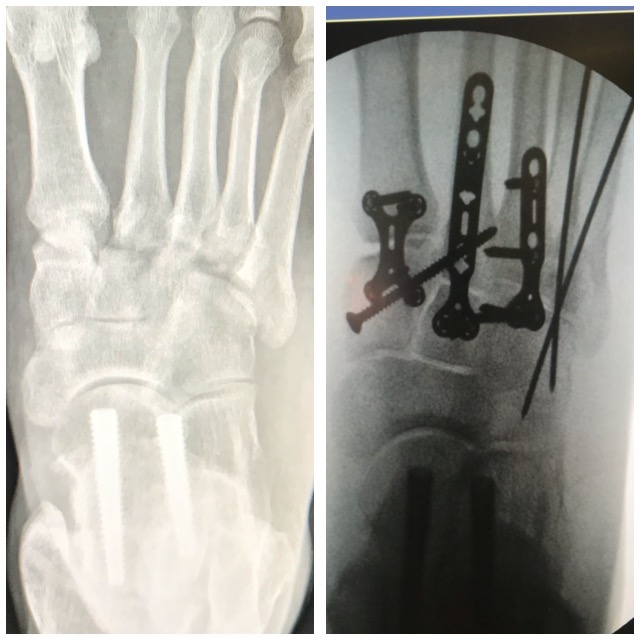

Jalkaterämurtuma

Ennen – jälkeen